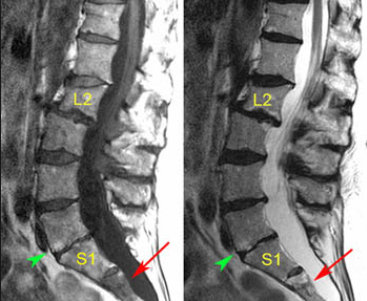

이 사건의 의뢰인은 상대방이 동석한 교통사고 피해자로서 사고 후 요통으로 ○○병원 응급실에 내원하였고 “제2요추폐쇄증후군” 진단을 받았다. 방사선 검사에서 “압박 골절”이 나타났습니다. 부상 초기에 척추의 추가 기형이 진행되거나 신경학적 증상이 나타나면 수술을 준비하고 며칠 동안 경과를 지켜보십시오. 다행스럽게도 통증은 신경학적 증상 없이 차차 가라앉았고, 정형외과를 통한 보존적 치료만이 상당 기간 지속되다가 치료가 종료되었다.

응급실 기록

진단